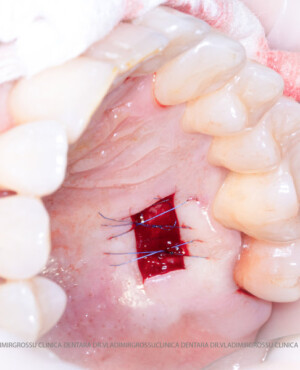

Adiția de gingie (gingivoplastia)

Aditia gingivală este o procedură chirurgicală ce corectează diverse probleme estetice și funcționale, cum ar fi recesiunea gingivală. În implantologia modernă, aditia de țesut moale este utilizată aproape în fiecare intervenție de inserție a implantului dentar pentru a asigura un aspect estetic natural și o bună integrare a implantului în cavitatea bucală.